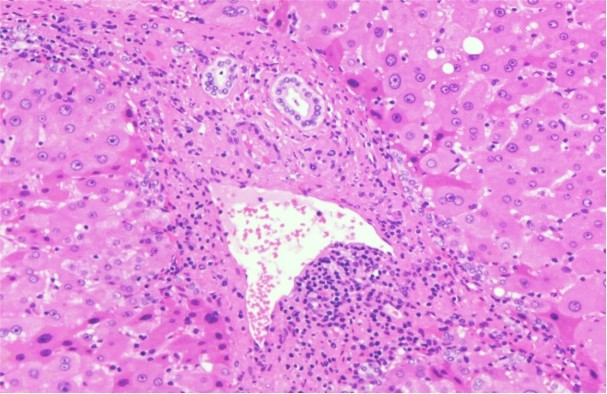

简而言之,在显微镜下,脂肪肝的主要组织学表现包括:

肝细胞脂肪变性、气球变性、小叶炎症和纤维化。此外,还可能出现其他病理学表现(如Mallory小体、巨大线粒体、糖原核、轻度的铁沉积以及局部的糖原贮积)。

(汇管区炎症:汇管区内有淋巴细胞及浆细胞浸润,通常库普弗细胞(肝内的巨噬细胞)也会增加。)